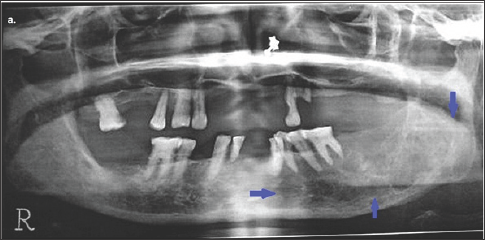

Figure 2: Orthopantomogram of the patient showing a multilocular osteolytic lesion in the left posterior region of lower jaw.

Orthopantomogram of the patient showing radiographic findings i.e. a multilocular osteolytic lesion in the left posterior region of lower jaw (as pointed out with blue arrows). There are ill defined area of bone erosion .Lesion mainly involves the alveolar ridge and is extended up to the inferior border of mandible. Teeth in left quadrant of lower jaw appear floating in the lesion.